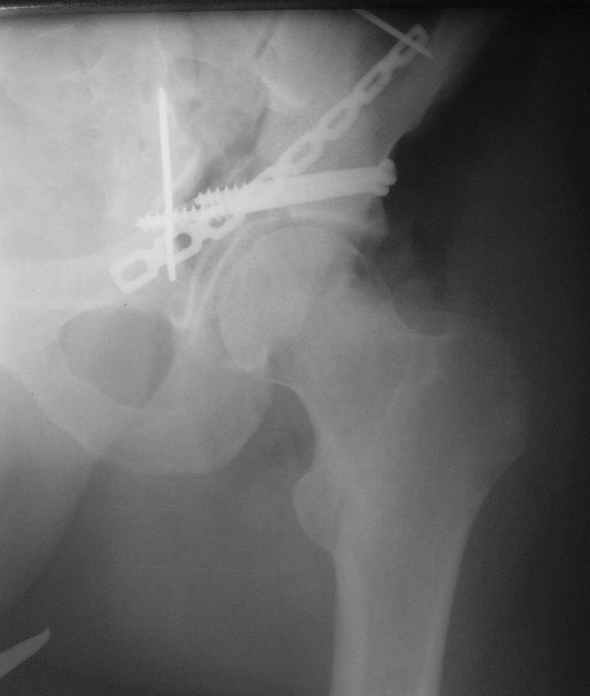

Anatoly F Lazarev 03 Сентябрь 2004, 22:18

Женя! Класный перелом. Отлично репонируется изнутри таза, но лучше фиксированть сзади. Классический перелом для двустороннего доступа.

Однако есть альтернатива. Репозиция из подвздошного доступа тазовыми щипцами с разнодлинными браншами или тазовым пистолетом, а фиксация задней колонны через седалищный бугор или тазрвыми винтами 4,5 или каннюлированными 6,5 или 7,3. По-моему я посылал на ортофорум такой снимок, когда жаловался на ишемический неврит седалищного нерва через сутки после операции. Не забудь про шейку бедра - мне кажется будет хорош длинный PFN любой фирмы, какую ты найдешь, а нет так UFN + miss a nail, как это здорово делают мои земляки - Ебурбуки. Пока.

Высылаю пример еще одного случая, остеосинтез пластиной из подвздошного доступа.

Анатолий, во второй презентации, какой Ваш диагноз, не поперечный ли перелом ацетабулум? Вы написали, Ваш доступ был подвздошный, по моему мнению, ваш доступ лимитировал Вас к anterior column и постоянно надо было держать в контроле за натяжением femoral artery and vein, иначе грозит закупоркой артерии или вены, (были и такие experience), при сгибании в тазобедренном суставе, которое ухудшает и так ухудшенный доступ. По-моему, если доступ расширить, т.е. formal Ilioinguinal approach то применить пластину подлиннее 12-14 дырок на pelvic brim, через первое окно Ilioinguinal approach, т.е. Symphisis side, после рассечения места прекрепления muscle rectus abdominus, где достаточно места для 4 шурупов, тогда таким образом фиксированный перелом держится более стабильно и 4.5 мм шурупы для колонн можно было бы пропустить через пластину кзади впадины.